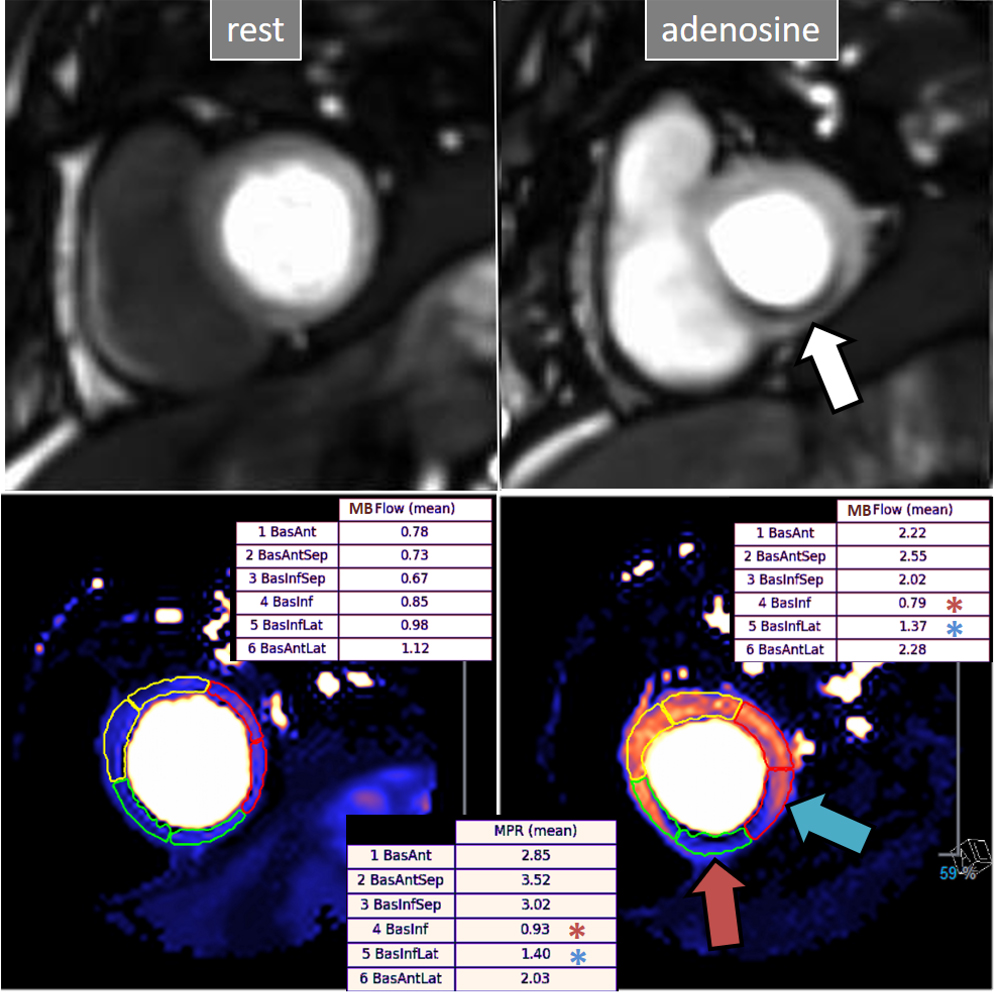

A study exploring further components of perfusion defects [36] showed that, besides extension and transmurality, also the presence of inducible contractile defect and, particularly, persistence of the defect throughout the full duration of the sequence, were also related with an adverse prognosis (Fig. 21). High values of an ischemic burden score based on these parameters showed prognostic value for clinical improvement after PCI in patients with chronic total coronary occlusion [48].

Fig. 21.Grading perfusion defects. The upper 2 panels present with the very last frames of perfusion studies where a persistent defect is seen at stress in the infero-lateral and antero-septal regions (asterisks). The lower 2 panels show corresponding end-systolic frames with conspicuous contractile adenosine-induced defects (arrows) in both regions.